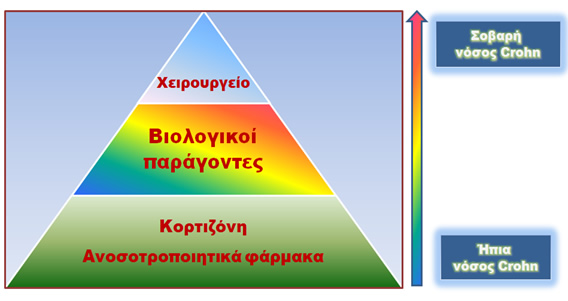

Παρά το γεγονός ότι η φαρμακευτική αντιμετώπιση της νόσου είναι η πρώτη επιλογή, η χειρουργική επέμβαση ενδείκνυται ή και επιβάλλεται σε συγκεκριμένες περιπτώσεις.

Καταρχήν πρέπει να τονιστεί ότι, μέχρι σήμερα, δεν υπάρχει θεραπεία για τη νόσο Crohn και, για το λόγο αυτό, οποιαδήποτε αντιμετώπισή της αποσκοπεί στην επίτευξη και στη διατήρηση μίας κατάστασης χωρίς ενεργό φλεγμονή με απώτερο στόχο τη μη υποτροπή της νόσου και την επίτευξη της επί μακρόν ύφεσης της. Η χειρουργική θεραπεία κρίνεται απαραίτητη για την αντιμετώπιση των επιπλοκών της νόσου Crohn (απόφραξη, συρίγγιο, αιμορραγία, κλπ).

Μόλις επιβεβαιωθεί μία τέτοια διάγνωση, η συντηρητική, δηλαδή η μη χειρουργική της αντιμετώπιση, είναι, κατά κανόνα, η πρώτη επιλογή του θεράποντος γιατρού, εκτός αν, όπως αναφέρθηκε παραπάνω, η κατάσταση του ασθενούς κρίνεται ως επείγουσα ή βαρέως επιπλεγμένη, οπότε η επέμβαση είναι αναπόφευκτη. Η συντηρητική διαχείριση της νόσου περιλαμβάνει πολλές φαρμακευτικές επιλογές τόσο για το αρχικό στάδιο της θεραπείας, όσο και για τα επόμενα, δηλαδή εκείνο της συντήρησης σε μία μη φλεγμονώδη κατάσταση ύφεσης και εκείνο της διατήρησης της ύφεσης και πρόληψης της υποτροπής.

Η επιλογή της πλέον κατάλληλης για την περίσταση θεραπείας συνήθως ανήκει στο θεράποντα γαστρεντερολόγο και γίνεται πάντοτε με γνώμονα το ιστορικό, την ηλικία, τη γενική κλινική εικόνα και το συγκεκριμένο τύπο με τον οποίο εμφανίζεται η νόσος Crohn στον εκάστοτε ασθενή. Η πιο κοινή φαρμακευτική αγωγή για την οξείες εξάρσεις της νόσου είναι ένα κορτικοστεροειδές, όπως η πρεδνιζόνη ή η μεθυλ-πρεδνιζολόνη, σε συνδυασμό με διάφορους αντιφλεγμονώδεις παράγοντες, ενώ ταυτόχρονα είναι αναγκαία η υιοθέτηση συγκεκριμένης διατροφής. Στη συνέχεια, προκειμένου να διατηρηθεί η ύφεση της νόσου και των συμπτωμάτων της, συχνά χορηγούνται στον ασθενή ειδικά ανοσοκατασταλτικά φάρμακα.

Η σύγχρονη ανοσοτροποποιητική αγωγή εναντίον της νόσου Crohn έχει, σήμερα, εμπλουτιστεί με τους ειδικούς βιολογικούς παράγοντες, οι οποίοι σε μέτριας σοβαρότητας και σοβαρές μορφές της νόσου, ιδιαίτερα σε ασθενείς με συρίγγια, έχουν βοηθήσει πολλούς ασθενείς. Αυτά τα ειδικά φάρμακα στοχεύουν συστατικά των κυττάρων της ανοσίας, όπως ένα παράγοντα που λέγεται TNF. Το Infliximab και το Humira, τα πλέον γνωστά και, στις HΠΑ, διαφημιζόμενα ακόμα και στην τηλεόραση, φάρμακα έχουν αλλάξει τη φυσική πορεία της νόσου Crohn. Η κατάχρησή τους, όμως, σε ασθενείς, που φαίνεται ότι θα ωφεληθούν από μία χειρουργική παρέμβαση, δεν είναι η ενδεδειγμένη τακτική. Εξάλλου, τα τελευταία δεδομένα υποστηρίζουν ότι μπορούν να χρησιμοποιηθούν και μετά το χειρουργείο ως προφύλαξη για τον ασθενή, προκειμένου να μην επέλθει σύντομα η έξαρση της νόσου.

Εάν εν γένει η συντηρητική αντιμετώπιση δεν είναι σε θέση να ανακουφίσει τον πόνο, την απόφραξη ή το σχηματισμό συριγγίου, τότε η χειρουργική επέμβαση καλείται να καλύψει αυτή την αδυναμία ή αποτυχία της φαρμακευτικής αγωγής και τελικά να βελτιώσει την κατάσταση της υγείας του ασθενούς.